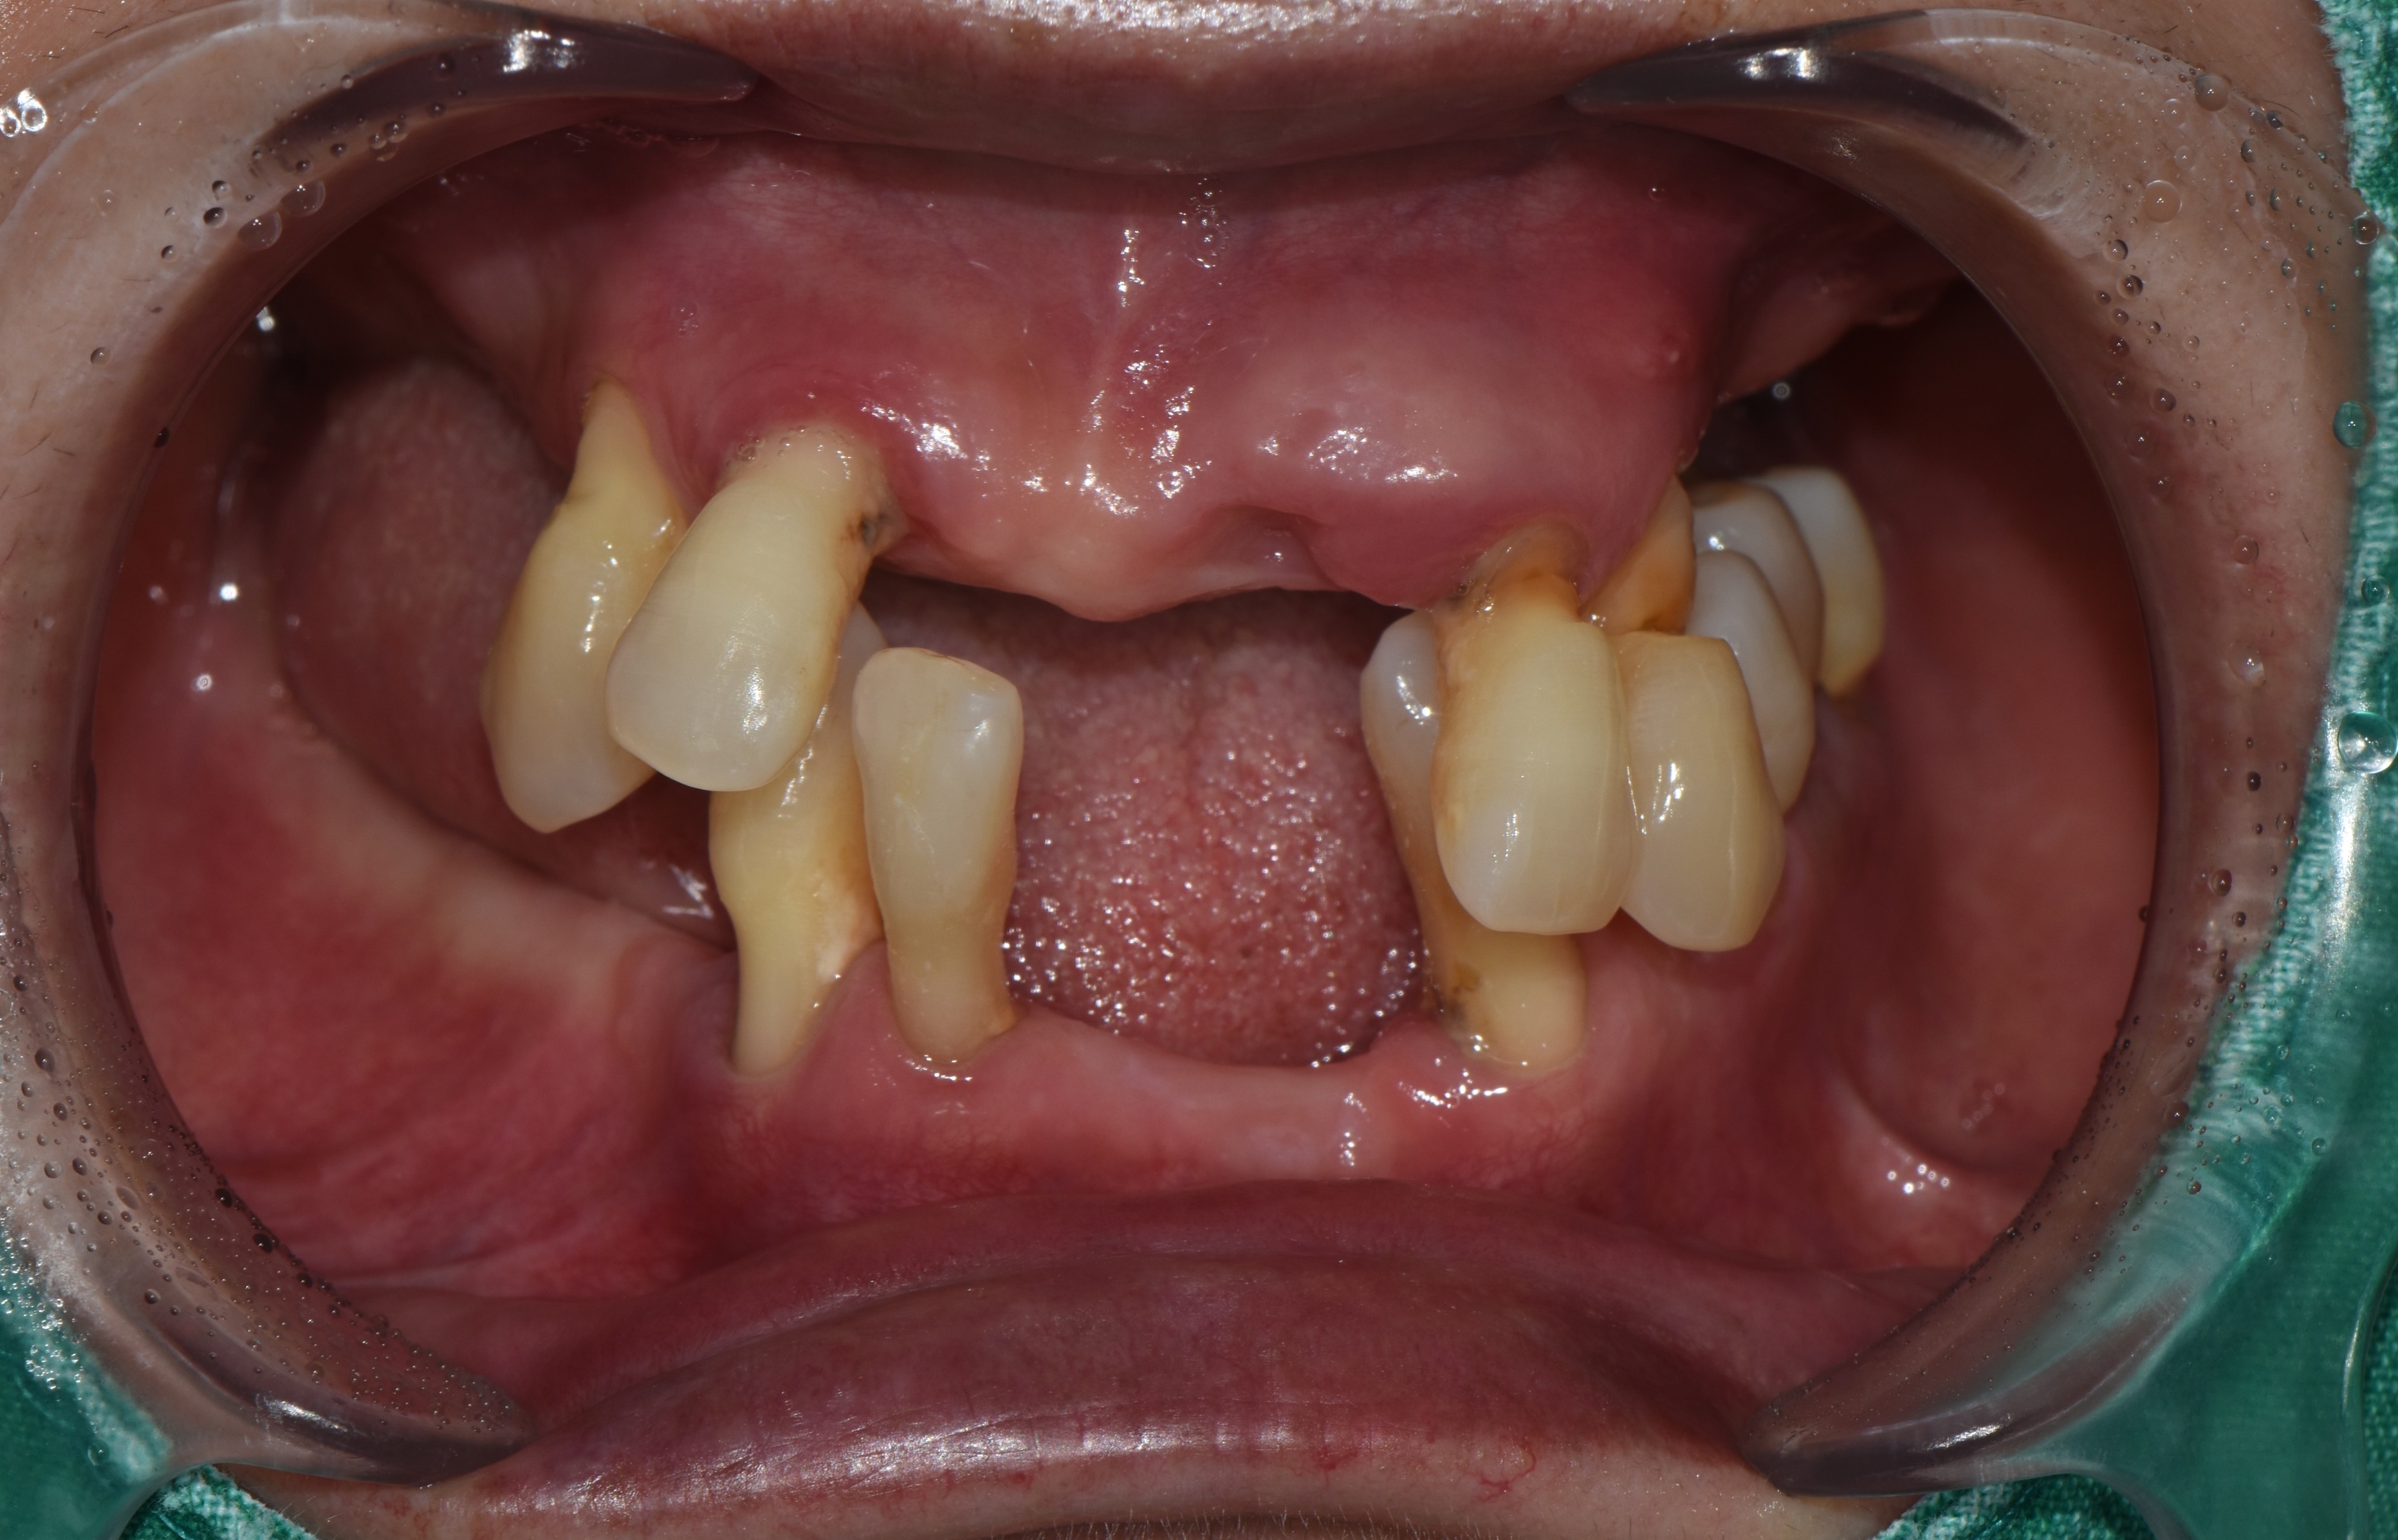

촬영일시: 2025.06.05